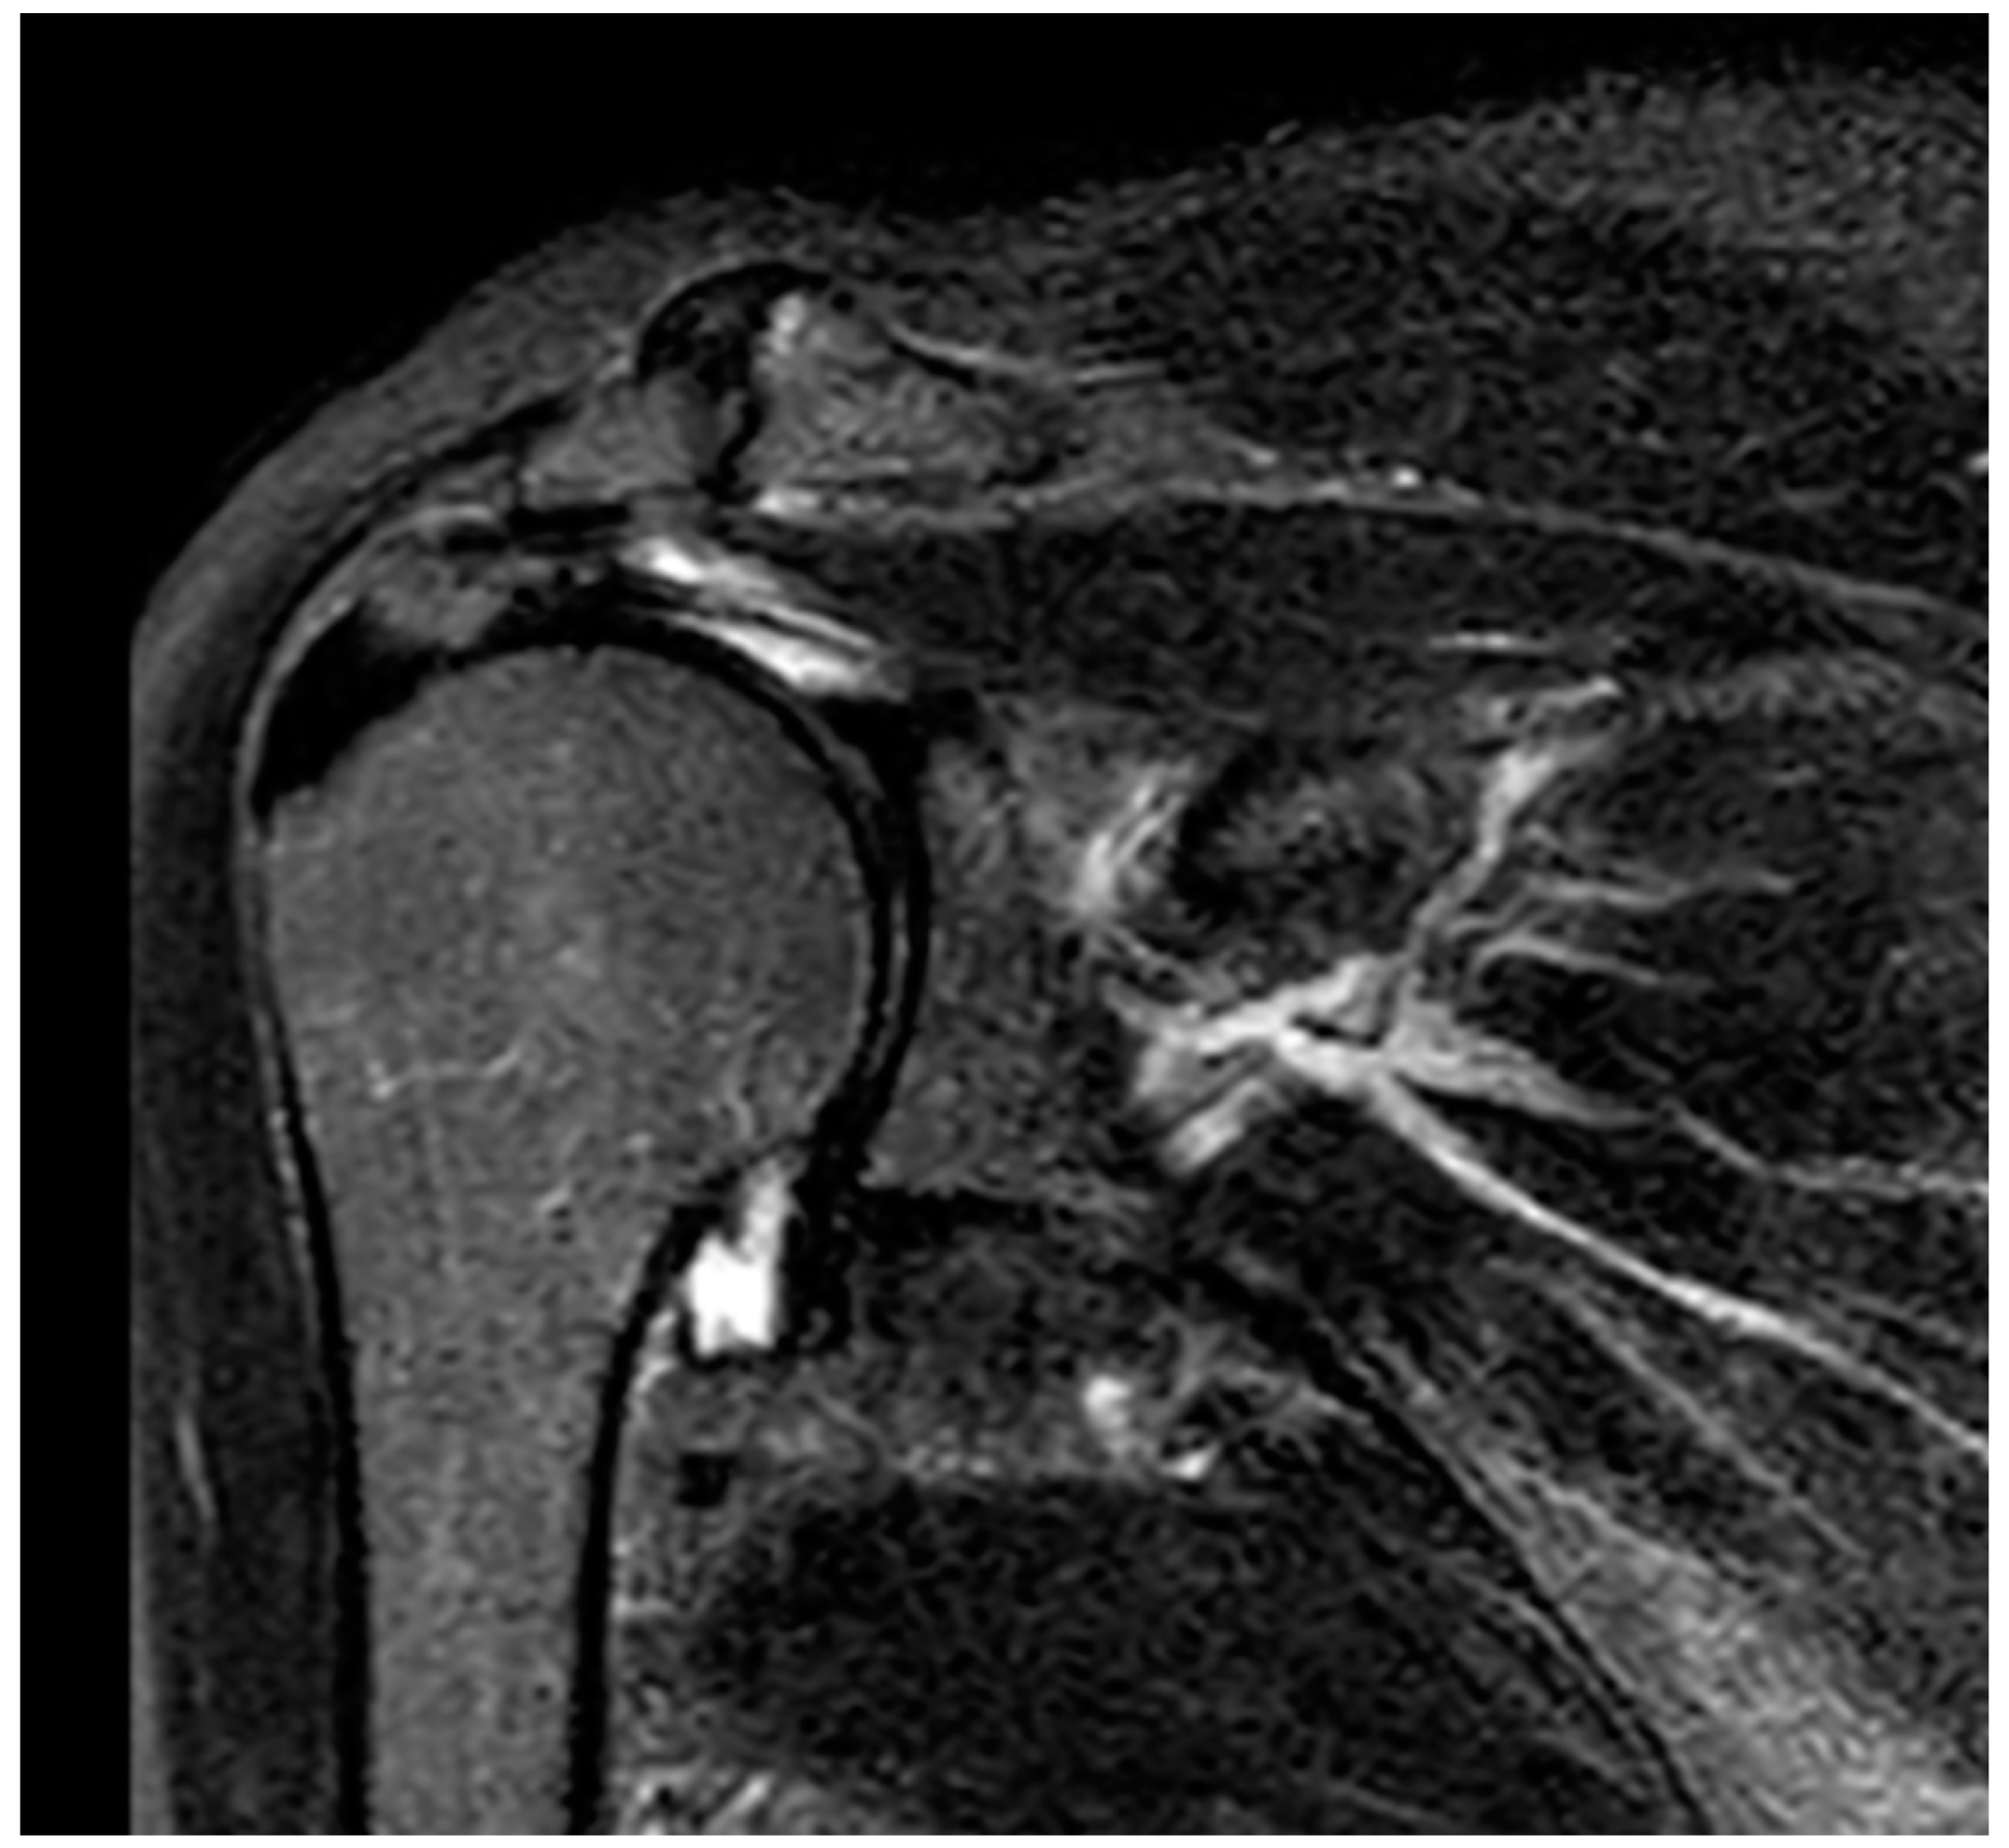

2. Detailed Case Description